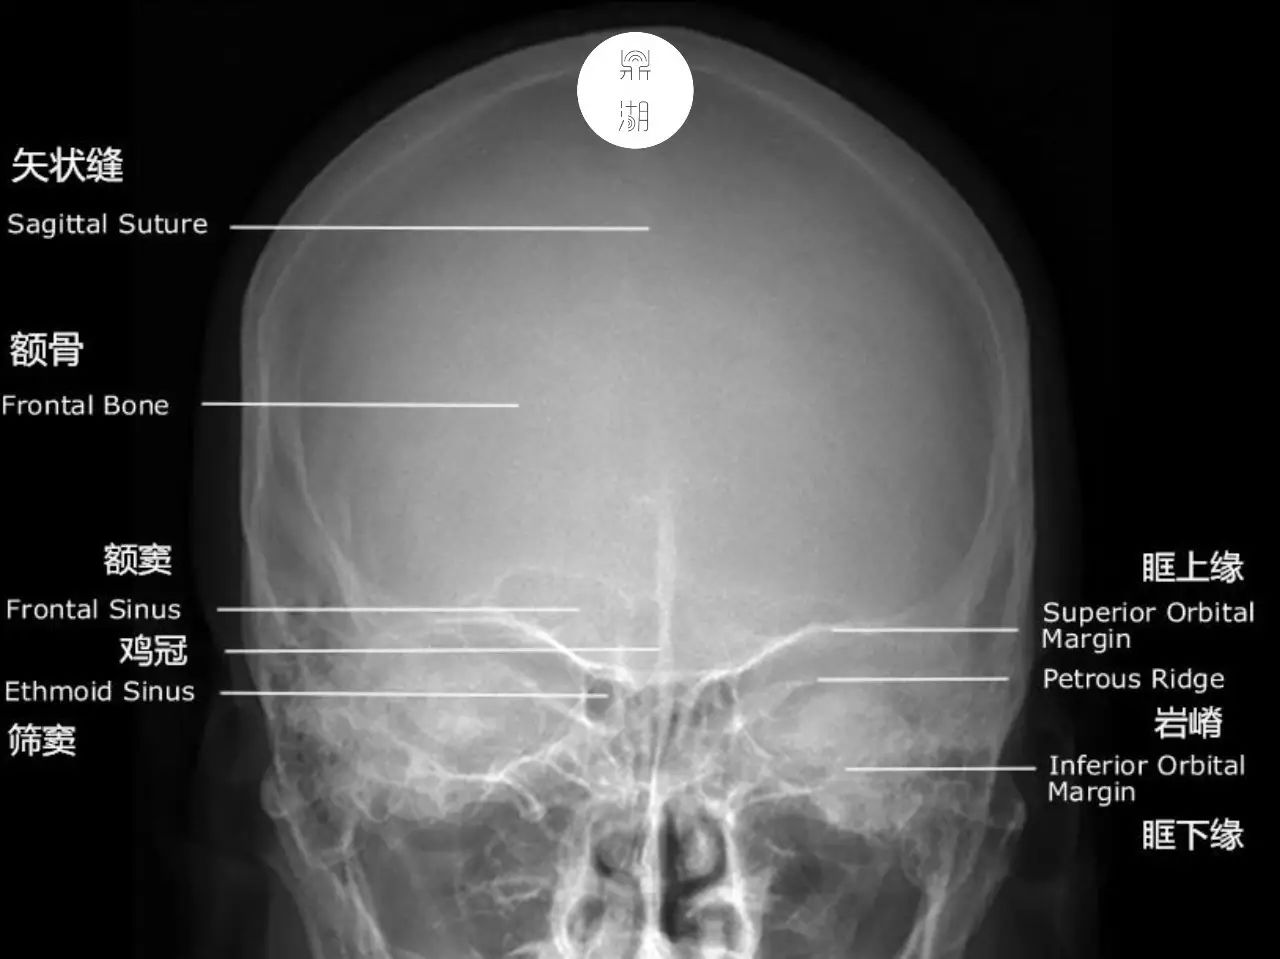

X线解剖 | 颅骨解剖

在临床工作中我们发现解剖知识的匮乏是很多医生和医学生存在的问题,医学院中解剖实践也非常有限,但是在临床工作中却要求我们对解剖学知识需要有一定程度的掌握。医学影像专业近年来发展飞速,扎实的影像解剖基础对于影像诊断的重要性不言而喻。没有牢固的影像解剖知识,就不能可靠的发现病变并进行准确的定位,甚至可能将正常解剖结构或正常变异误认为病变,接下来的一段时间里,我们会进行总结学习,将影像解剖一点一点过清楚、学明白,在帮助大家巩固知识点的同时,我们自己也进行学习与总结。